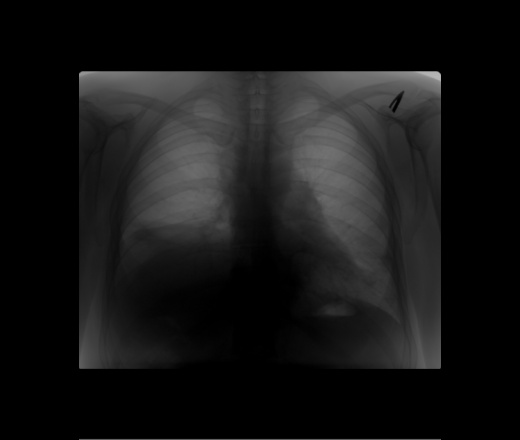

Релаксация правого купола с дисковидными ателектазами

Сделали пр.бок. В ан-зе лимфома Ходжкина слева. Нет ли сейчас картины центрального справа? Ателектаз S3 cправа

Слева -динамика положительная. Справа, считаю, пневмония в S9 не разрешилась. Дисковидные ателектазы в ср. доле справа. Увеличение паратрахеальных лф. узлов. Релаксация правого купола лиафрагмы.

С лф. узлами, видимо, погорячилась. Это удлиненная, изогнутая аорта.

Рекомендовала конс.онколога все же и КТ легких. Уж больно много всего там. А тень слева, это смещение сердца?